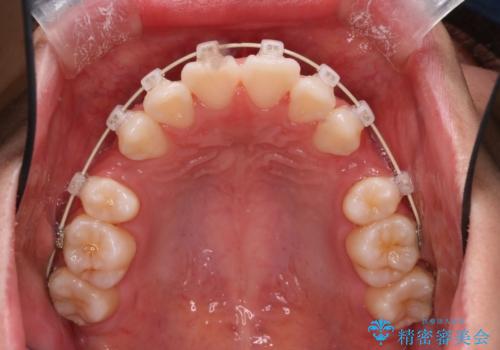

- 矯正装置

- 審美装置

上顎両側小臼歯を抜歯して治療を行い、突出感も大幅に改善しました。